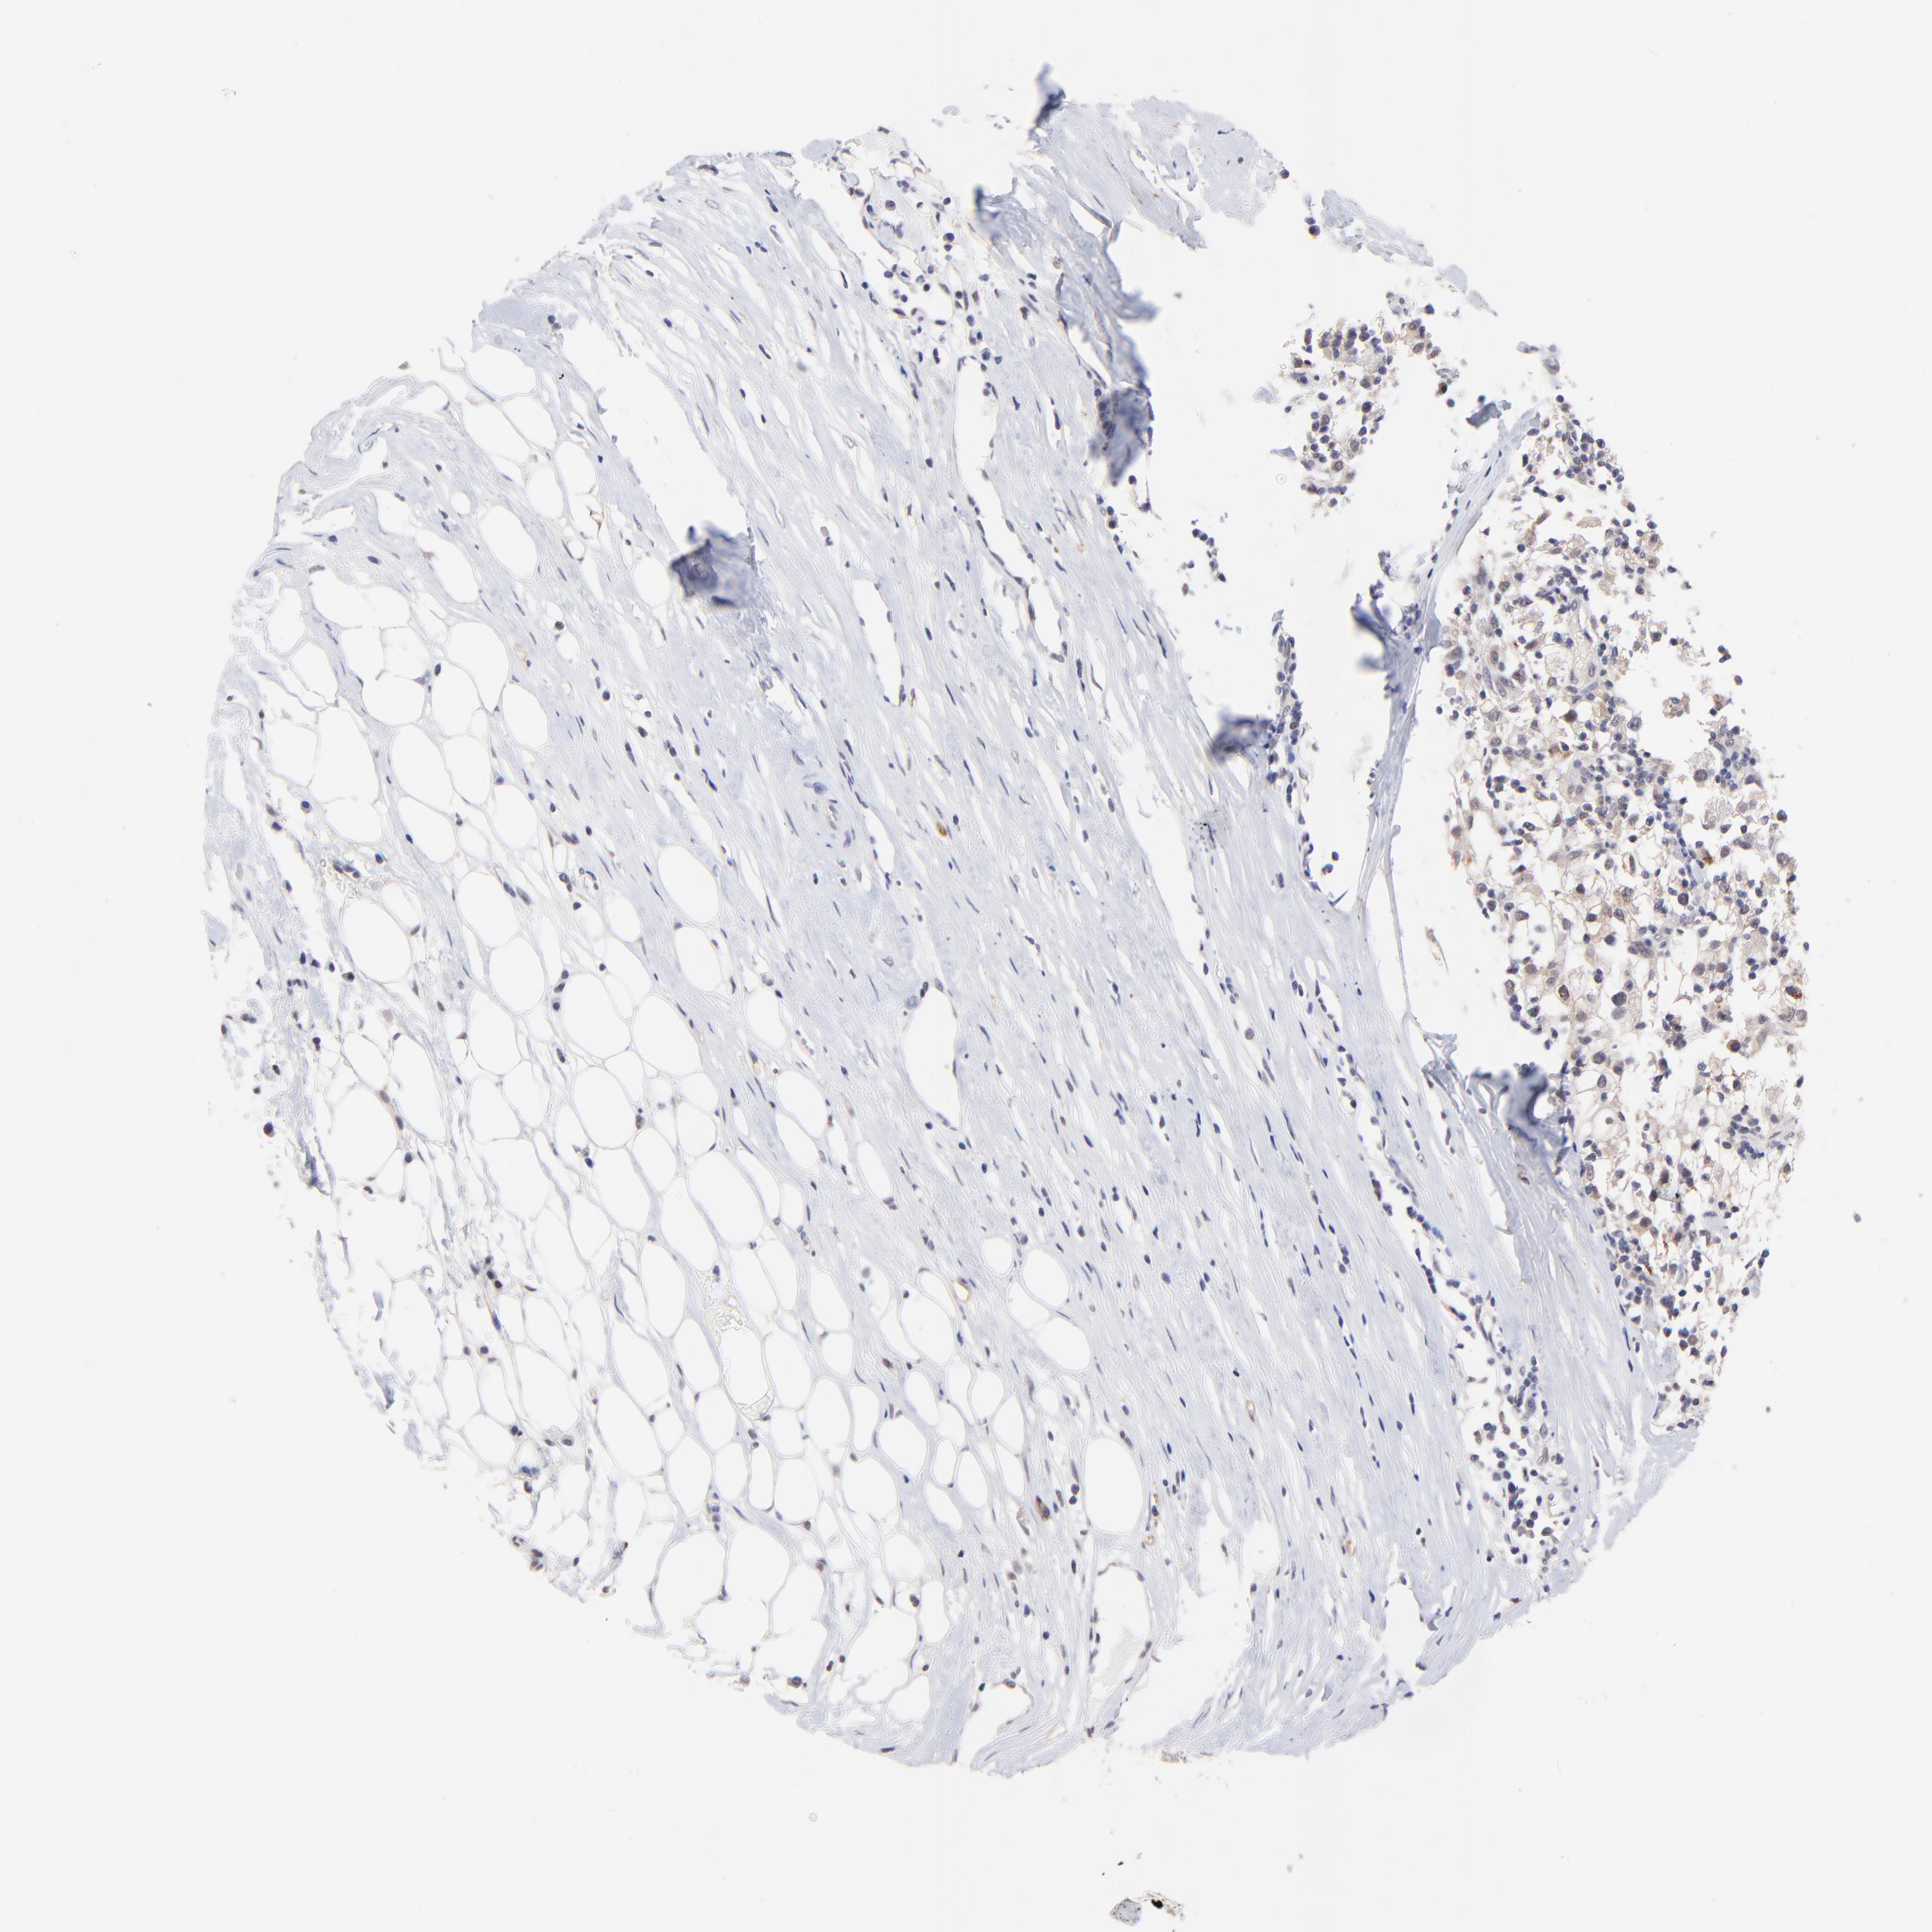

KIDNEY RENAL CLEAR CELL CARCINOMA (VALIDATION) - Interactive survival scatter ploti

The Survival Scatter plot shows the clinical status (i.e. dead or alive) for all individuals in the patient cohort, based on the same data that underlies the corresponding Kaplan-Meier plots. Patients that are alive at last time for follow-up are shown in blue and patients who have died during the study are shown in red.

The x-axis shows the expression levels (FPKM) of the investigated gene in the tumor tissue at the time of diagnosis. The y-axis shows the follow-up time after diagnosis (years). Both axes are complimented with kernel density curves demonstrating the data density over the axes. The top density plot shows the expression levels (FPKM) distribution among dead (red) and alive patients (blue). The right density plot shows the data density of the survived years of dead patients with high and low expression levels respectively, stratified using the cutoff indicated by the vertical dashed line through the Survival Scatter plot. This cutoff is automatically defined based on the FPKM cutoff that minimizes the p-score. The cutoff can be changed by dragging the vertical line or by entering a cutoff value in the square labeled "Current cut-off".

Under the Survival Scatter plot the p-score landscape (black curve; left axis) is shown together with dead median separation (red curve; right axis). Dead median separation is the difference in median mRNA expression between patients who have died with high and low expression, respectively. It is calculated as follows: median FPKM expression of dead patients with high expression - median FPKM expression of dead patients with low expression. This is intended to aid the user in visually exploring custom cutoffs and the associated p-scores and dead median separation.

Individual patient data is displayed and can be filtered by clicking on one or more of the category buttons on the top of the page. Categories describing expression level and patient information include: high, low, alive, dead, female, male and tumor stages. The scale of the x-axis can be toggled between linear and log-scale by clicking on the "x log" button. Mouse-over function shows TCGA ID, patient information and mRNA expression (FPKM) for each patient.

& Survival analysisi

Kaplan-Meier plots summarize results from analysis of correlation between mRNA expression level and patient survival. Patients were divided based on level of expression into one of the two groups "low" (under cut off) or "high" (over cut off). X-axis shows time for survival (years) and y-axis shows the probability of survival, where 1.0 corresponds to 100 percent.

ZNF764 is not prognostic in Kidney Renal Clear Cell Carcinoma (validation)

Best expression cut offi

Based on the FPKM value of each gene, patients were classified into two groups and association between prognosis (survival) and gene expression (FPKM) was examined. The best expression cut-off refers the FPKM value that yields maximal difference with regard to survival between the two groups at the lowest log-rank P-value. Best expression cut-off was selected based on survival analysis .

When clicking on this number, the vertical dashed line indicating cut-off, the interactive survival plot, and the Kaplan-Meier curve will be adjusted to show results based on the best expression cut-off.

: 6.54

P scorei

Log-rank P value for Kaplan-Meier plot showing results from analysis of correlation between mRNA expression level and patient survival.

N/A

TCGA RNA samplesi

RNA-seq data is reported as average FPKM (number Fragments Per Kilobase of exon per Million reads), generated by the The Cancer Genome Atlas (TCGA) .

Normal distribution across the dataset is visualized with box plots, shown as median and 25th and 75th percentiles. Points are displayed as outliers if they are above or below 1.5 times the interquartile range. FPKM values of the individual samples are presented next to the box plot.

Average pTPM 6.4

Number of samples 100